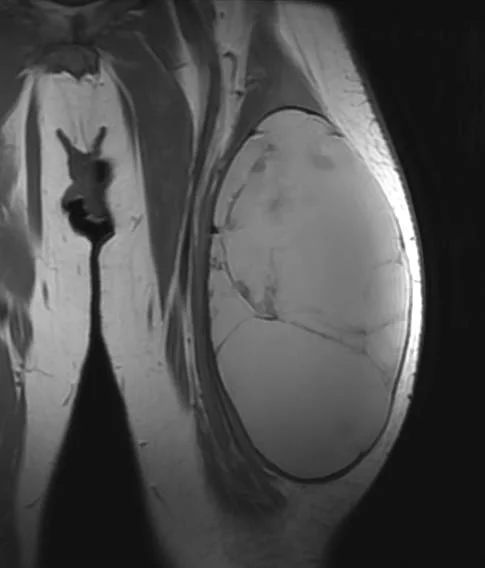

This 62 year old man presented with thigh pain and swelling. MRI imaging showed a large mass within the quadriceps muscle (vastus lateralis). Biopsy was performed at the time of initial evaluation and confirmed a high grade undifferentiated sarcoma. The tumor was localized to the thigh (Stage III).

He completed 5 weeks of preoperative radiation and then underwent surgery. Below are MRI images of his tumor. The first image below shows the change in the tumor before and after radiation. It is not uncommon for sarcomas to enlarge during radiation therapy. This is thought to be due to cell death from radiation resulting in hemorrhage

The next two images above show the extent of the tumor at the time of surgery. The last image demonstrates how most of the mass is fluid and blood, as the large bulk of the mass does not take up contrast and remains dark.